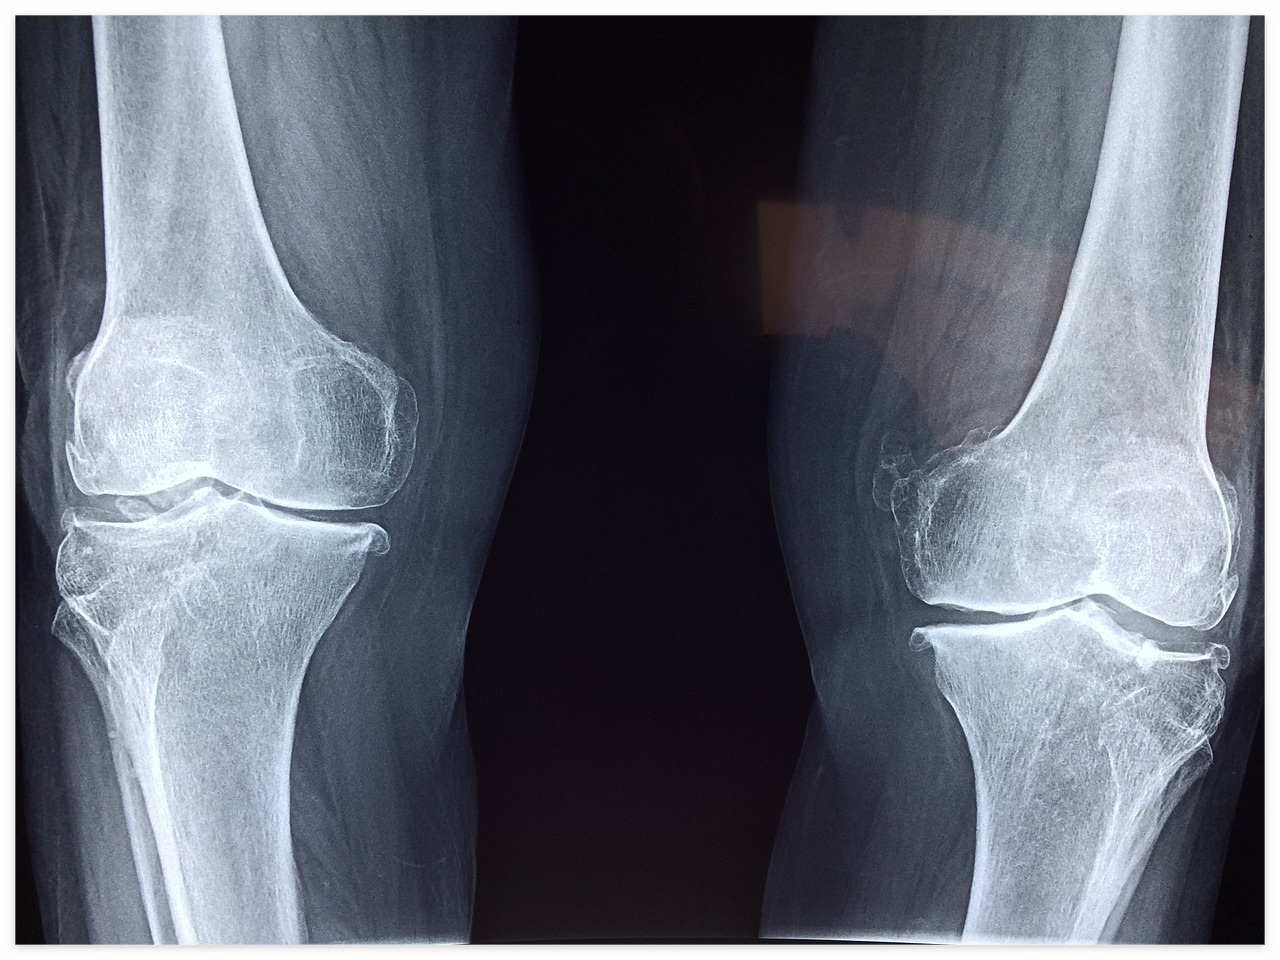

b) 관절 손상이나 변형이 심할 때

관절 연골이 심하게 손상되어 움직일 때마다 통증이 생기거나 관절 기능이 저하된 경우, 특히 퇴행성 관절염이 많이 진행된 상태에서는 수술이 필요할 수 있습니다.

c) 관절 변형이 발생한 경우

관절이 변형되어 통증과 움직임 제한이 있을 때, 관절을 교정하거나 고정하는 수술이 필요할 수 있습니다.